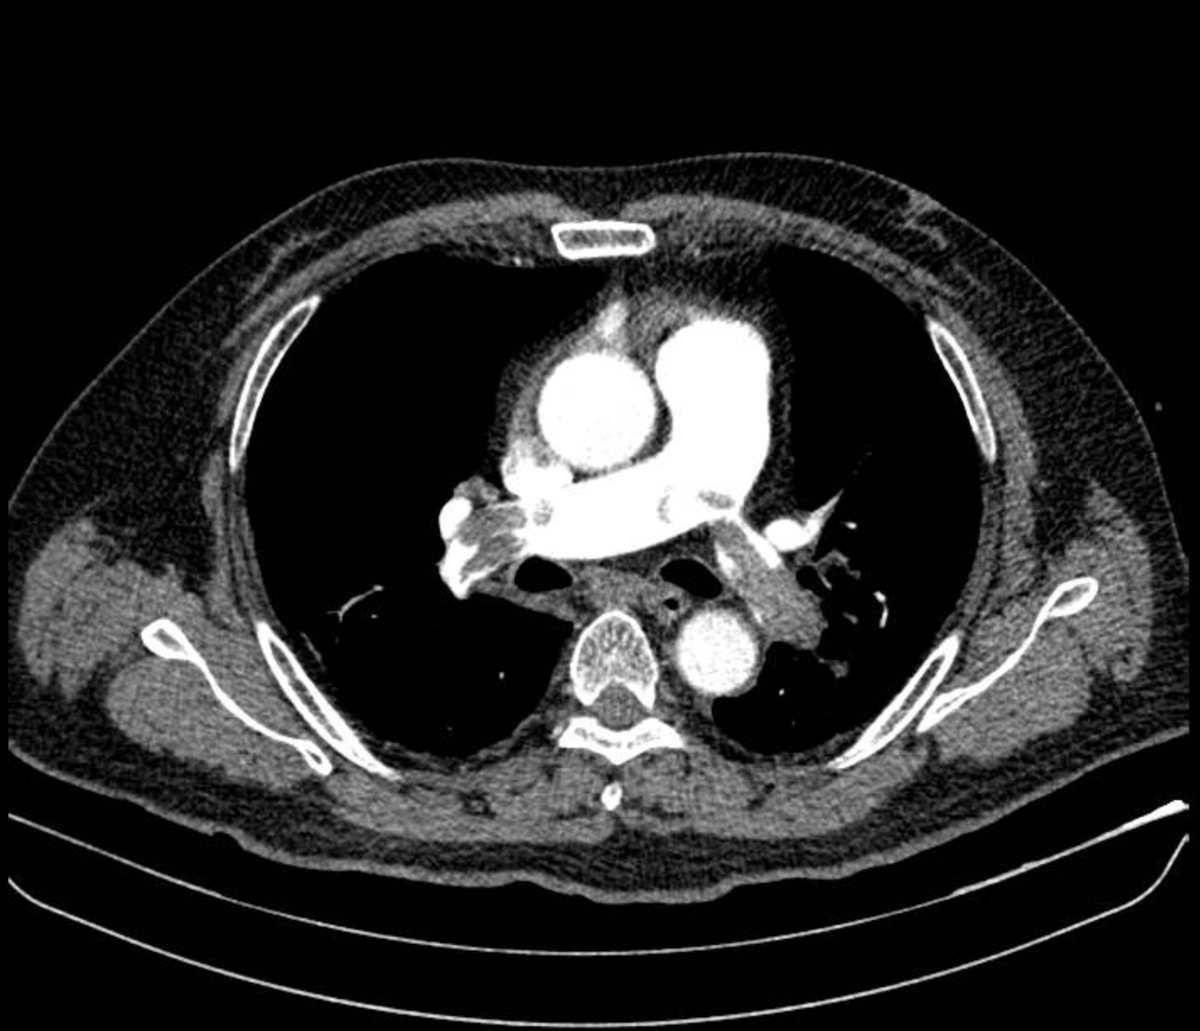

Hình ảnh chụp CT mạch máu phổi cho thấy huyết khối lớn bít tắc động mạch phổi hai bên. Ảnh BV

Bệnh nhân nhanh chóng được dùng thuốc vận mạch để ổn định huyết áp, chụp CT mạch máu phổi. Kết quả cho thấy huyết khối lớn bít tắc hai nhánh động mạch phổi. Các bác sĩ khoa Cấp cứu phối hợp Khoa Hồi sức tích cực xác định đây là trường hợp sốc tắc nghẽn do thuyên tắc phổi nguy cơ cao.